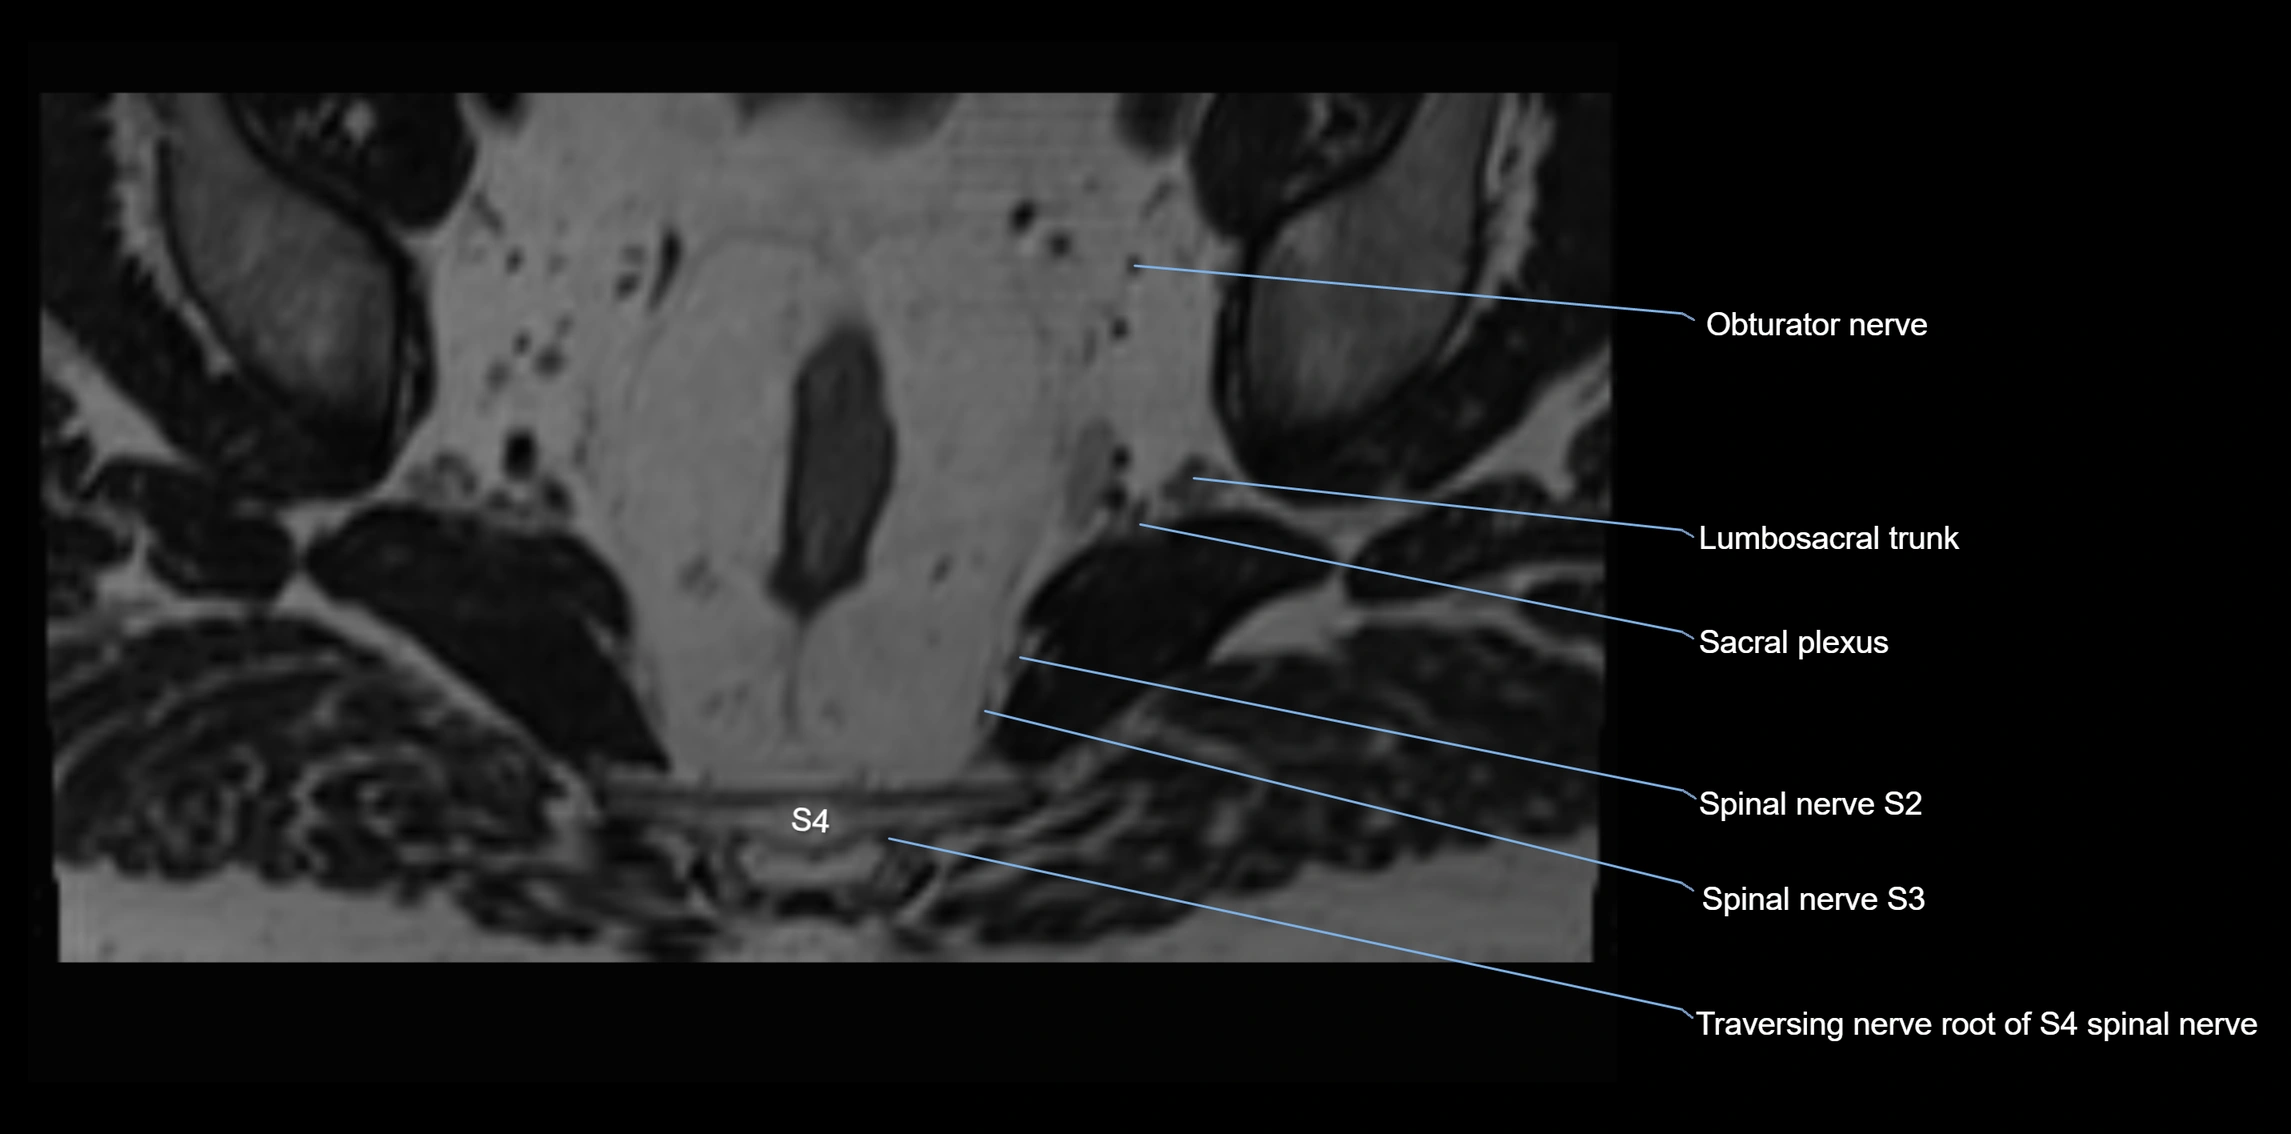

MRI Appearance

T1-weighted images:

• Nerve appears as a very thin low-to-intermediate signal intensity structure

• Surrounded by bright fat, aiding visualization

T2-weighted images:

• Nerve shows intermediate to mildly hyperintense signal compared to muscle

• Pathological involvement appears brighter

STIR (Short Tau Inversion Recovery):

• Normal nerve appears dark

• Inflamed or entrapped nerve appears bright hyperintense

T1 Fat-Sat Post-Contrast:

• Normal nerve enhances minimally

• Pathologic nerve (neuritis, entrapment, tumor infiltration) shows focal or diffuse enhancement

3D T2 SPACE / CISS:

• Nerve appears intermediate to mildly hyperintense compared to muscle

• Surrounded by bright fat or CSF, improving visualization

• Best sequence for mapping small pelvic nerves such as the anococcygeal